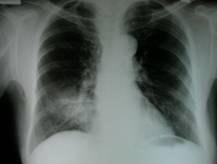

Kartagener由支气管扩张、慢性鼻窦炎或鼻息肉、内脏反位三联征组成,主要以反复呼吸道化脓性感染、咯血为特征的支气管扩张症状及副鼻窦炎和右位心。Kartagener,又称为内脏逆位-鼻窦炎-支气管扩张综合征,或称家族性支气管扩张,属于先天性常染色体隐性遗传疾病,具有家族遗传倾向,可同代或隔代发病,其父母多有近亲婚姻史。